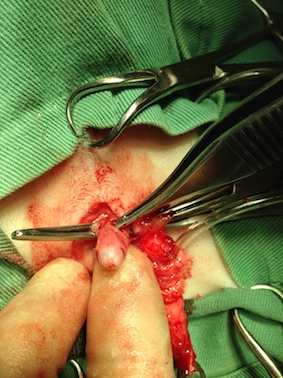

この写真はペニスが尿道の奥深くに埋没していた非常にまれな症例です。

膀胱結石から尿道に結石が詰まった症例の手術

尿道を露出したところ

これは尿道に結石がたんまり詰まっていた症例です。これではいくら尿道カテーテルで結石を膀胱に戻そうとしても戻るわけがありません。

ペニスの粘膜を反転して尿道と接続。

現在の状態。尿道がよく見えませんが、昔からの尿道を皮膚に縫合する術式より優れているのは、

尿道の皮膚開口部が狭窄することが無い。開口部付近の皮膚が荒れることも無い。

ほぼメスのような構造になる点など。